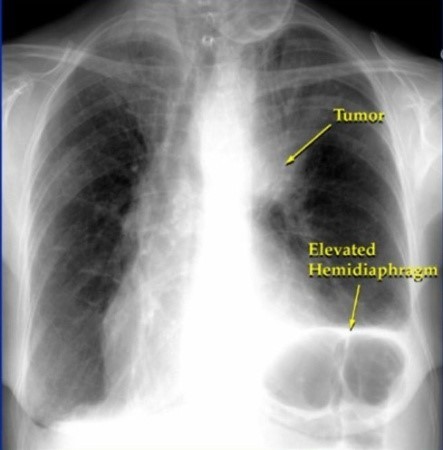

- 호흡 곤란 및 가슴 통증

- 설명: 폐렴의 가장 심각하고 중요한 증상입니다. 폐에 염증이 생겨 폐 기능이 떨어지면서 숨쉬기 힘들어지며, 얕고 빠른 호흡을 하게 됩니다. 심한 경우 가슴에 통증을 느끼거나, 옆구리가 결리는 듯한 느낌을 받을 수 있습니다.